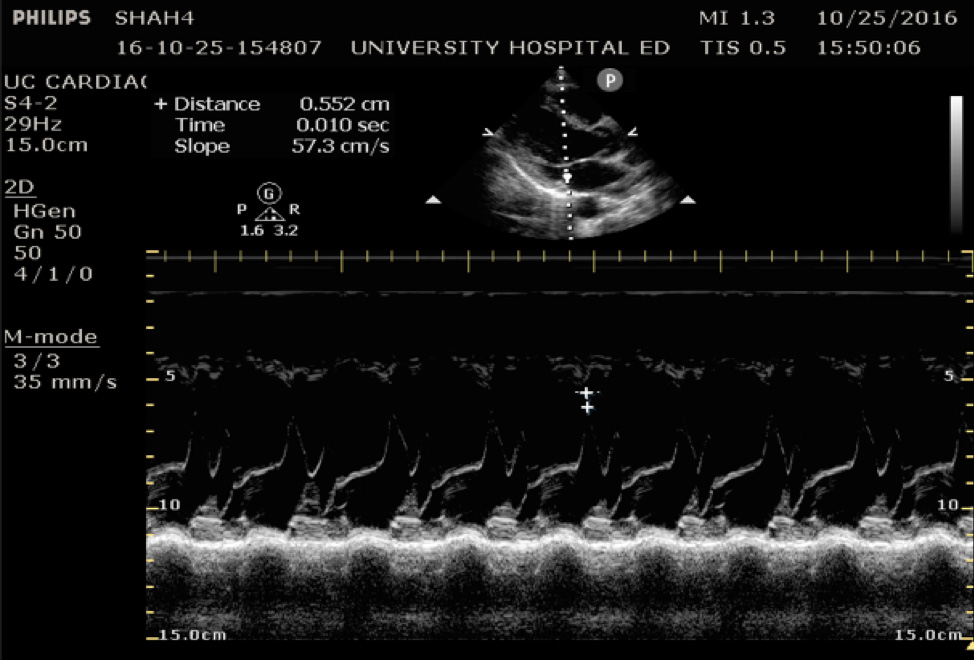

EPSS

In the parasternal long view, an M-mode line is placed through the anterior mitral leaflet. The distance is between the leaflet tip and interventricular septum is measured during the point in early diastole where the tip of the leaflet is closest to the septum. (Figure 5) A value of >7mm is highly suggestive of depressed cardiac contractility or low EF. (Figure 6) Note that this measurement is invalidated by the presence of valvular pathology or left ventricular/septal hypertrophy. This method is also not valid for assessing for hypercontractility.

Figure 5. Image of normal EPSS measurement measured from the tip of the anterior mitral valve leaflet in diastole to the interventricular septum